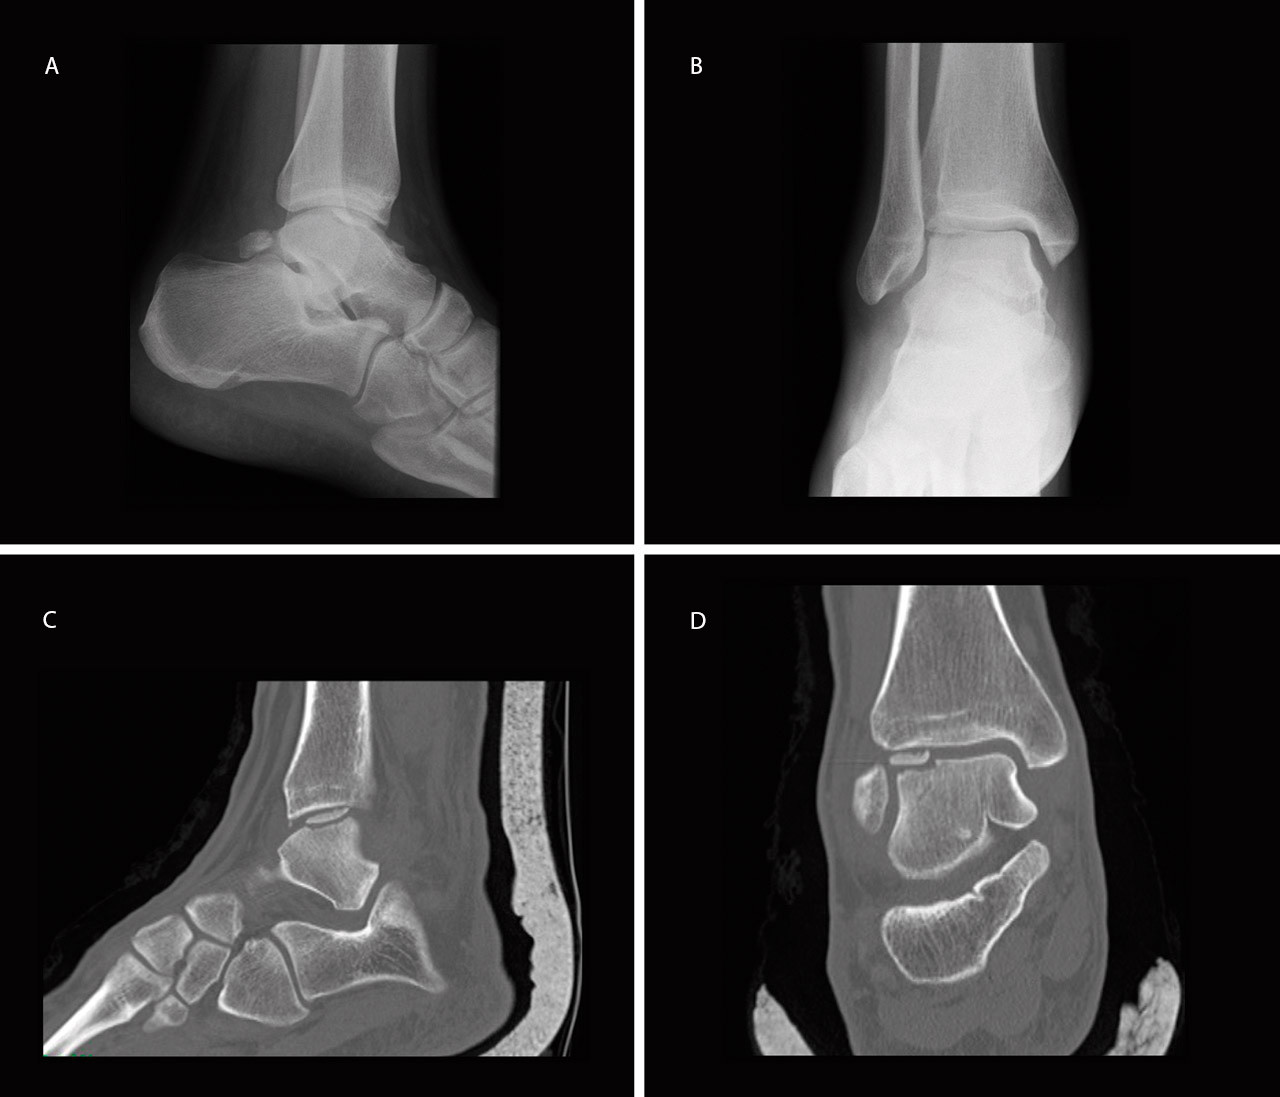

Se trata de un varón de 22 años de edad, atendido en urgencias por dolor en tobillo derecho tras mecanismo de supinación e inversión forzada en el tobillo derecho. Fue diagnosticado inicialmente de esguince de tobillo de grado II-III e inmovilizado con una férula suropédica durante 3 semanas. Inicialmente no se realizó ninguna prueba complementaria debido a que el paciente no cumplía los criterios de Ottawa. Cuando inició la deambulación, debido a la persistencia de dolor, tumefacción y limitación en la flexión dorsal del tobillo, a las 4 semanas se realizó una radiografía (Rx) en la que se observó un defecto óseo compatible con una LOT en la cúpula astragalina anteroexterna del tobillo (Figuras 1A y 1B). A los 5 días se realizó una tomografía computarizada (TC) que mostró una fractura osteocondral con fragmento de 1 cm2 volteado 180° (cartílago articular en contacto con hueso subcondral del talus), en la zona 3 de Elias(5)(Figuras 1C y 1D), por lo que se decidió realizar tratamiento quirúrgico.